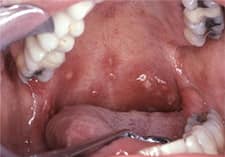

Ulser Mata Ikan

Ulser 3 Lapis Mata Ikan A Walk To Remember

Cara Hilangkan Ulser Mata Ikan Di Mulut Anak Cara Oatmeal Food

Jangan Anggap Semua Luka Di Mulut Adalah Sariawan Ini Alasannya